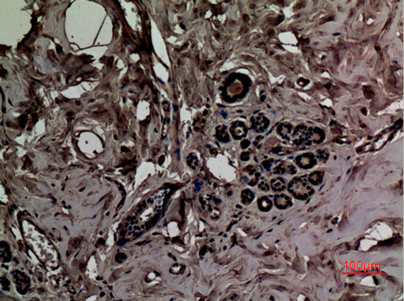

Immunohistochemical analysis of paraffin-embedded human-breast, antibody was diluted at 1:100